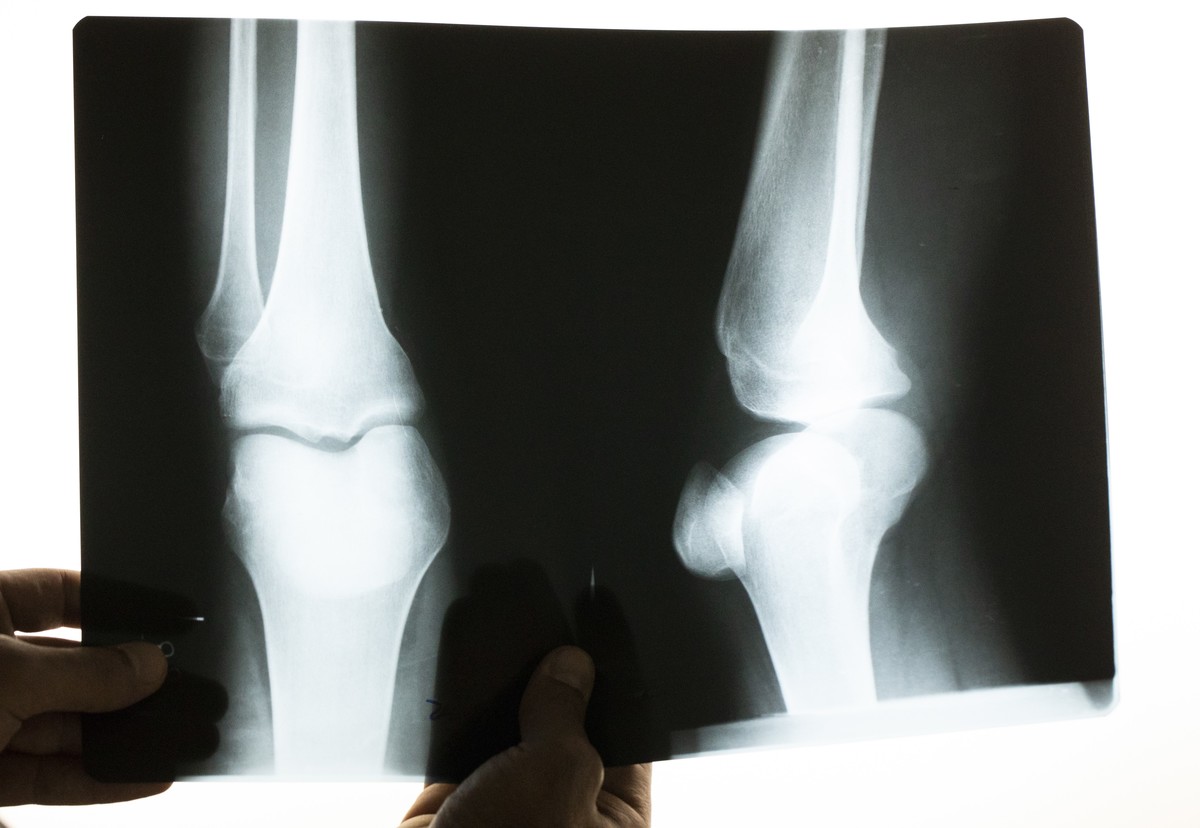

Body Hair Was Removed With X-Rays

Using X-rays to remove body hair in the early 20th century was seen as a permanent solution to shaving. Why worry about grabbing your razor and foam on a busy morning but you could radiate the problem away?

The only problem with this treatment for hair removal was that many patients got cancer. This is because in order to remove all the hair they wanted to permanently, they would have to be exposed to radiation for more than 20 hours!